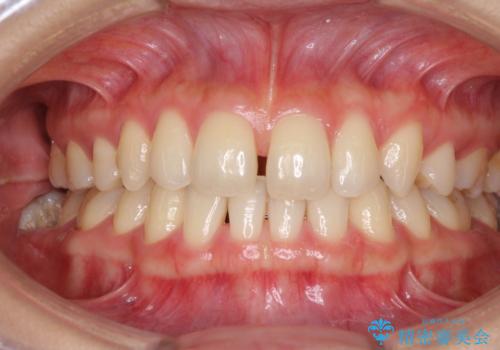

- 以前の矯正治療の後戻りにより、上の前歯にスペースができたことを気にして来院された患者様です。

インビザラインを用いて前歯のスペースを閉じつつ、上下の咬み合わせを構築していくこととしました。